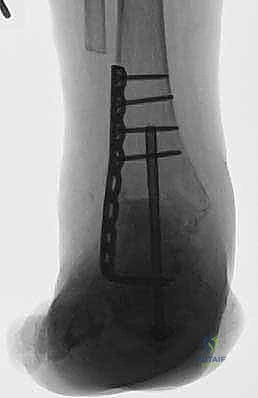

لماذا صفيحة الشفرة الجانبية (Lateral Blade Plate)؟

تاريخياً، كان جراحو العظام يستخدمون مسامير طويلة يتم إدخالها من باطن القدم عبر الكعب وصولاً إلى الساق (Intramedullary Nails) لدمج هذه المفاصل. رغم أن هذه الطريقة لا تزال مستخدمة، إلا أن الأستاذ الدكتور محمد هطيف يفضل في كثير من الحالات المعقدة استخدام صفيحة الشفرة الجانبية (Lateral Blade Plate). لماذا؟

- الصلابة الميكانيكية الفائقة: صفيحة الشفرة الجانبية توفر ثباتاً استثنائياً. الشفرة التي يتم إدخالها في عظمة الكعب تمنع أي حركة دورانية، في حين يتم تثبيت باقي الصفيحة بقوة في عظمة الساق.

- الضغط المباشر (Compression): لكي تلتئم العظام وتندمج، يجب أن يتم ضغطها معاً بقوة. التصميم الهندسي لهذه الصفيحة يسمح للجراح بتطبيق ضغط هائل على الأسطح المفصلية المقطوعة، مما يحفز الخلايا العظمية على النمو والالتحام.

- الحفاظ على باطن القدم: على عكس المسمار النخاعي الذي يتطلب إحداث شق في باطن القدم (مما قد يسبب ألماً مزمناً عند المشي لاحقاً)، يتم تركيب الصفيحة من الجانب، مما يحافظ على سلامة الأنسجة الحساسة في باطن القدم.

- التعامل مع التشوهات الشديدة: في الحالات التي يكون فيها الكاحل منزاحاً بشدة، توفر الصفيحة الجانبية مرونة أكبر للجراح لإعادة العظام إلى محورها الصحيح وتثبيتها بقوة.

الخطوة الخامسة: تركيب صفيحة الشفرة الجانبية

يتم تشكيل الصفيحة المعدنية (المصنوعة من التيتانيوم أو الفولاذ المقاوم للصدأ الطبي) لتطابق الانحناء التشريحي لساق وقدم المريض. يتم إدخال "الشفرة" الخاصة بالصفيحة بدقة في عظمة الكعب (Calcaneus). ثم يتم تثبيت الجزء العلوي من الصفيحة على عظمة الساق (Tibia) باستخدام مسامير قوية.

الخطوة السادسة: الضغط النهائي والتثبيت

باستخدام أداة شد خاصة، يقوم الجراح بسحب الصفيحة لتوليد ضغط ميكانيكي هائل على المفاصل المجهزة. هذا الضغط يغلق أي فجوات ويضمن تلامساً محكماً بين العظام. يتم إضافة مسامير إضافية تعبر المفاصل (Lag Screws) لزيادة الثبات.